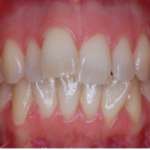

L’utilizzo dell’allineamento pre-protesico seguito da terapia restaurativa con tecniche adesive consente di proporre ai pazienti piani di trattamento con un approccio minimamente invasivo